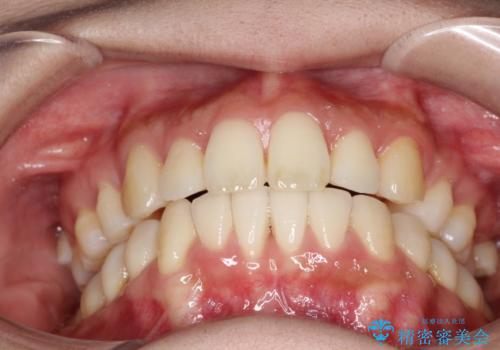

裏側からの矯正であったため、表側に比べて少し治療期間を要しました。

目立たずに矯正治療を終えることができ、満足していただけました。